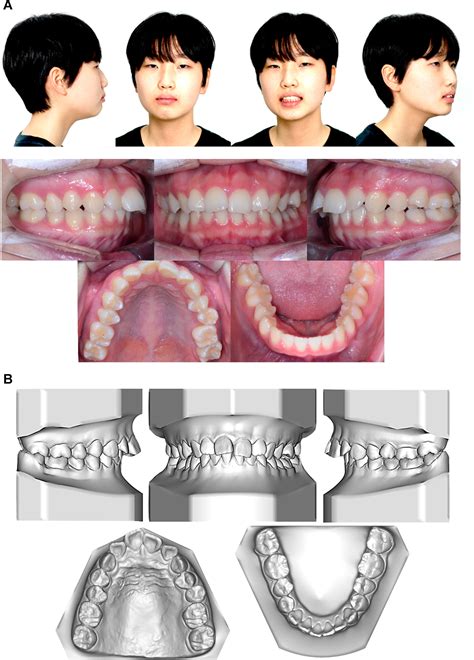

The progression of ICR can lead to significant changes in a person’s bite and facial profile. As the condyle shrinks, the lower jaw (mandible) shifts backward and upward, often resulting in an anterior open bite, where the front teeth no longer meet even when the back teeth are touching. This change can occur rapidly or slowly, often causing distress to patients who notice their smile or facial structure shifting unexpectedly.

• Progressive open bite: A noticeable gap developing between top and bottom front teeth.

• Facial asymmetry: A receding chin or a chin that appears to be drifting to one side.